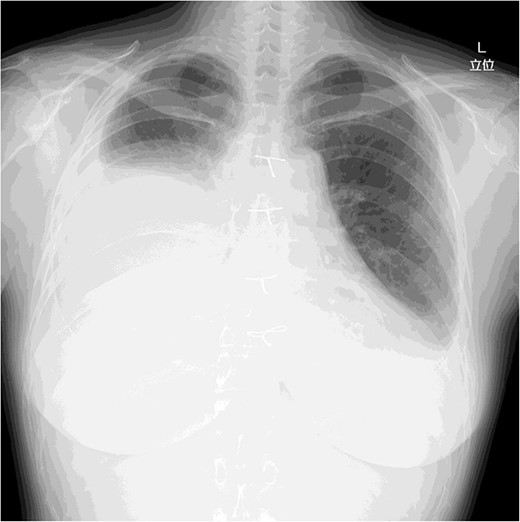

On post-operative day 17, she visited our hospital for a routine follow-up, and her chest X-ray revealed a massive right pleural effusion (Fig. 3). Therefore, she was re-admitted to our hospital and right chest drainage was performed. Milky and turbid fluid was drained with an amount of ~3100 ml. The biochemical analysis of pleural fluid revealed a triglyceride level of 1420 mg/dl, and we confirmed a diagnosis of chylothorax. She received fasting and total parenteral nutrition. The fluid via chest tubes returned to be clear with its amount of <200 ml for a day.

Chest X-ray on post-operative day 17 revealing massive pleural effusion.